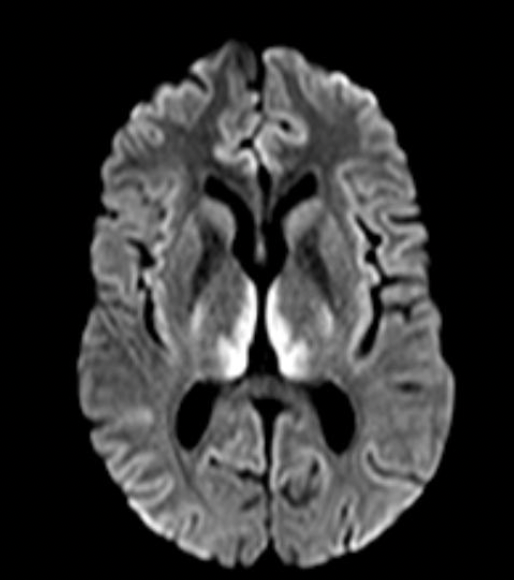

Imagem 1

Complicações neurológicas da Fludarabina